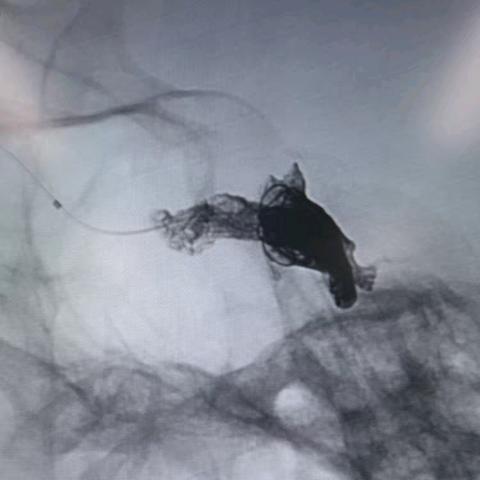

徐建国,男,45岁,额叶动静脉畸形-动静脉入路

01-26 264阅读